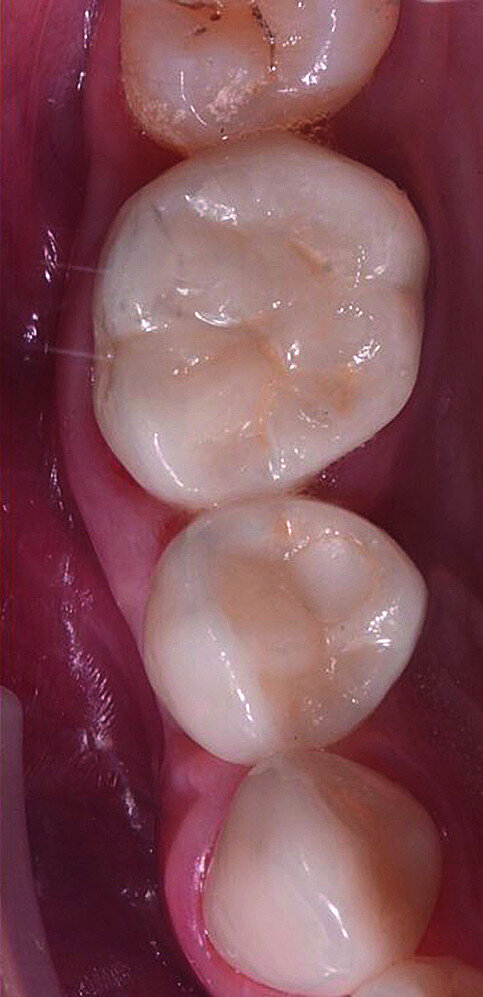

In March 2018, four months after the surgery, the prosthetic phase was started. An impression was taken with an intraoral scanner (CS 3600, Carestream Dental) using scan bodies for an impression at the implant head (MegaGen; Figs. 11a & b). The information was sent to the Anatomic Lab, where a crown was designed using a CAD programme. After the design of the crown had been finished, the information was sent to a milling machine (Amann Girrbach) and the crown was milled (Fig. 12). One week after the preparation, the definitive crown in monolithic zirconia was attached and the occlusion tested using T-Scan technology (Tekscan; Figs. 13a–c & 14).